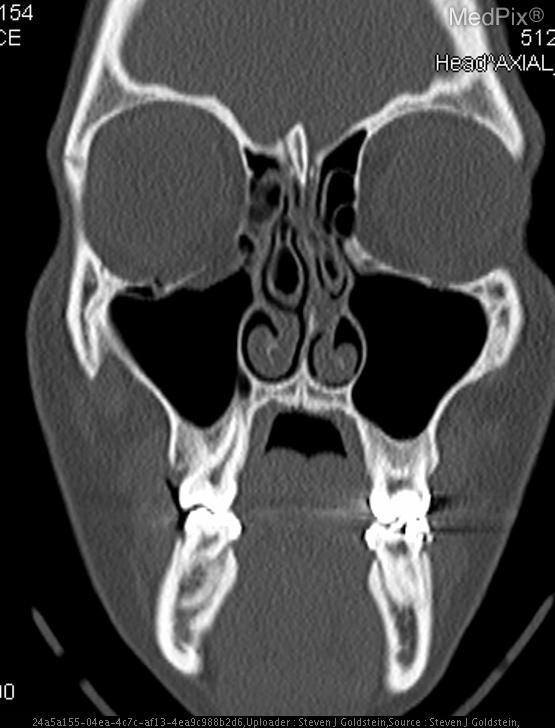

- Coronal CT image shows discontinuity of the orbital floor on the image-left (patient-right) side.

- Herniation of orbital fat and partial inferior displacement of soft tissue into the maxillary sinus on the image-left (patient-right).

- Air-fluid level within the right maxillary sinus (image-left side), consistent with hemorrhage or fluid collection.

- Intact orbital floor on the image-right (patient-left) side.

- Globes are intact bilaterally, without evidence of rupture or significant intraorbital hematoma.

- Nasal septum roughly midline; ethmoid air cells and remaining paranasal sinuses are clear.

- No intracranial abnormalities visible at this coronal slice level.